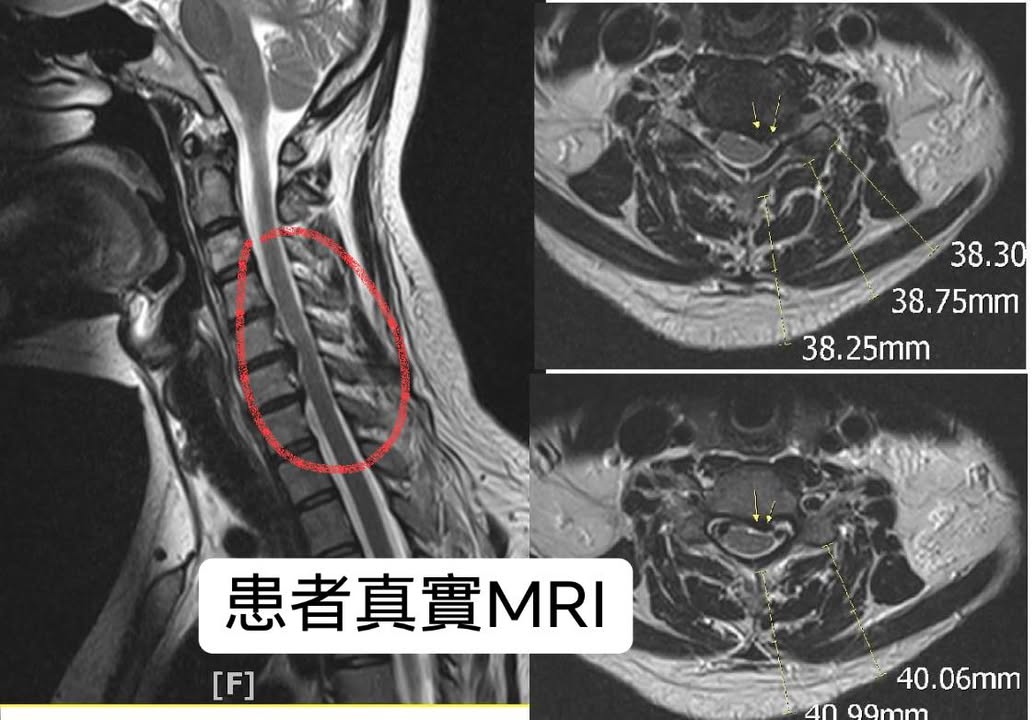

困擾四年多的手麻跟胸悶與心悸,今年開始嚴重惡化,在當地骨科骨科電療熱療做過好幾個月,也在中壢壢新醫院打過一次消炎止痛藥,整天持續疼痛晚上睡覺痛,坐車有時候10分鐘甚至躺5分鐘開始頭暈與胸悶,拍過MRI發現頸椎過直合併椎間盤突出,但症狀除了神經根卡壓,更有交感神經嚴重症狀,特別是胸悶跟頭暈脹痛,雖然骨科醫師說不嚴重先復健但效果一直不如預期,也不是傳統壓迫脊髓要開大刀的患者,端詳過片子跟理學檢查與交感神經量表,我下了以下的診斷

⭕️診斷:交感神經型頸椎病